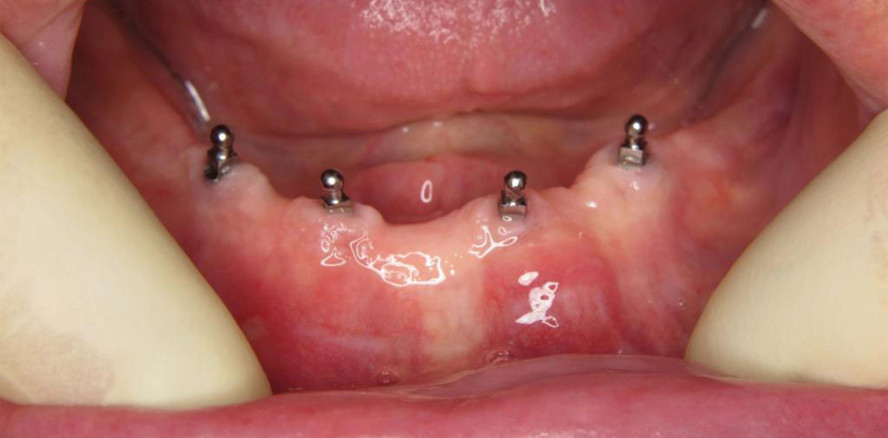

Zur Stabilisierung von Totalprothesen kann der Einsatz von Implantaten hilfreich sein. Zur Auswahl stehen neben herkömmlichen zweiteiligen Implantaten auch einteilige Mini-Implantate, zum Beispiel das MDI-System von Condent. Ein großer Vorteil von Mini-Implantaten ist die sehr einfache Pflegbarkeit der Kugelköpfe der Implantate. Im Vergleich zu Retentionselementen wie Locator, Teleskopen oder Steg verbessert die einfache Pflegbarkeit der intraoralen Mini-Implantat-Anteile die Prognose. Bei Locatorversorgungen kann beim Hausbesuch im Alten- oder Pflegeheim immer wieder beobachtet werden, dass ein empfundener schlechter Halt oft nur darauf zurückzuführen ist, dass sich in die okklusale Mulde des Locatoraufbaus Speisereste impaktierten, die ein Einrasten der im Zahnersatz vorhandenen Retentionselemente in die Endposition erschweren oder unmöglich machen. Manchmal fällt es geriatrischen Patienten zunehmend schwerer, die für das Einsetzen erforderliche Anpresskraft der Retentionselemente zu überwinden, und so kommt es beim Kauen dazu, dass sich Speisereste unter die Prothese in die Retentionselemente einlagern. Diese sind für das Pflegepersonal nicht nur schwer zu erkennen, sondern auch oft nur durch Anwendung einer Sonde entfernbar.

Bei Mini-Implantat-Versorgungen, wie beispielsweise mit dem schon erwähnten Condent MDI-System, bestehen die auswechselbaren Retentionselemente aus einfach zu wechselnden Gummiringen, die auch im Vergleich zu anderen, herkömmlichen Retentionselementen die Folgekosten gering halten.

Auch die finanziellen Möglichkeiten der Patienten können einer Verbesserung des Prothesenhalts durch Implantate entgegensprechen. In den meisten Fällen kann durch den Einsatz von Mini-Implantaten die Gesamtversorgung mit vier Mini-Implantaten im Unterkiefer zu den Kosten, die nur einem herkömmlichen Implantat entsprechen, realisiert werden. Die Weiterverwendung von vorhandenem Zahnersatz durch Einarbeiten der Retentionselemente trägt ebenfalls zur Kostenreduktion für die Gesamtversorgung bei.

Transgingivale Insertion

Mini-Implantate können meist minimalinvasiv transgingival inseriert werden und eignen sich gerade für Patienten mit eingeschränktem gesundheitlichem Allgemeinzustand aufgrund der geringen Belastung durch den operativen Vorgang. Die Kontraindikationen bezüglich der Allgemeinanamnese entsprechen denen der herkömmlichen Implantologie, jedoch lassen sich mit Mini-Implantaten auch Fälle mit durch Kieferkammresorption eingetretenem geringerem Knochenangebot ohne Kieferkammaugmentation versorgen.